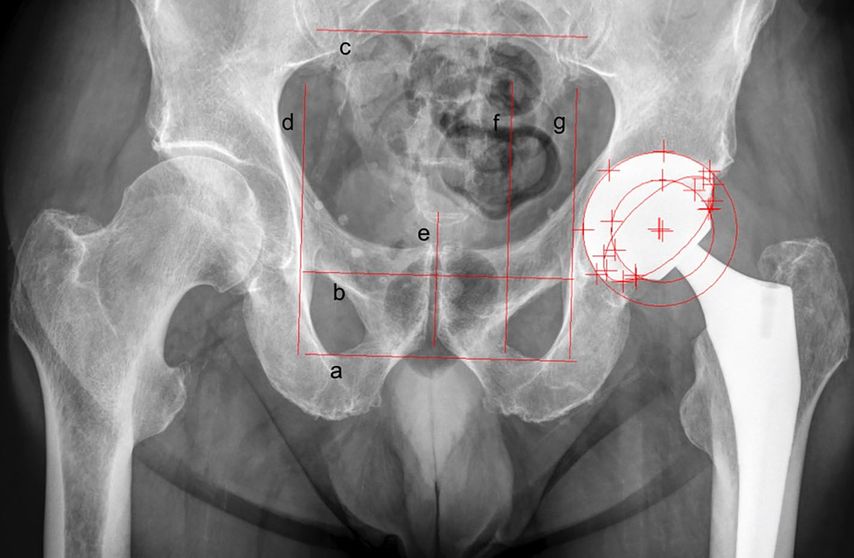

EBRA-Cup ermöglicht es, die Migration der Pfanne sowohl in Längs- (Kranial-/Kaudalwanderung) als auch in Querrichtung (Medial-/Lateralwanderung) zu messen.10 Hierzu werden je drei Tangenten in horizontaler und vertikaler Ausrichtung an bestimmte knöcherne Strukturen des Beckens im Röntgenbild angelegt (Abb.1). Während sich die Basislinie dabei an den Foramina obturatoria oder den kaudalen Konturen des Beckens (Tuber ischiadicum) orientiert, kann die mittlere horizontale Linie tangential am oberen Rand des Os pubis oder alternativ an den Foramina obturatoria eingezeichnet werden. Die obere Tangente soll einem der Foramina sacralia aufliegen. Im Gegensatz hierzu werden die beiden lateralen vertikalen Tangenten an den Foramina obturatoria oder am äußersten Punkt der jeweiligen Linea iliopectinea angelegt. Zuletzt markiert die vertikale Foramenlinie die Seite der zu vermessenden Pfanne. Eine weitere kürzere vertikale Linie kennzeichnet die Symphyse (Symphysenlinie).

Abb. 1: Migrationsanalyse der Pfanne mit EBRA-Cup im Standard-Hüftübersichtsröntgen: a) Basislinie, b) mittlere Linie, c) obere Linie, d) linke Linie, e) Symphysenlinie, f) Foramenlinie, g) rechte Linie